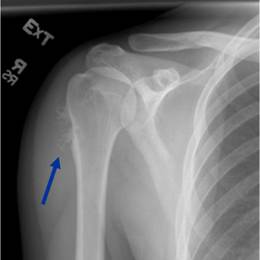

- • 50% of all cases occur in the long bone of the arm, called the humerus.

Radiographic imaging is used to help form a diagnosis. These include X-Ray, MRI, CT and Bone Scans.

An example of a X-Ray is shown.